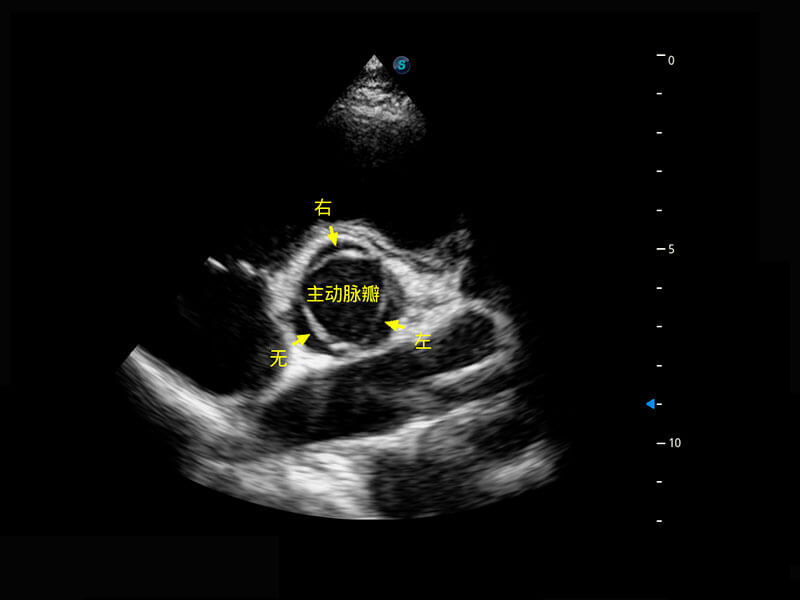

生殖健康

P60优异的图像质量搭载专科探头,在妇科基础疾病的诊断、卵泡生长的监测、输卵管通畅情况的判别等方面为您提供生殖应用方案。

• 腔内三维-宫内节育器

• 腔内三维-光影成像